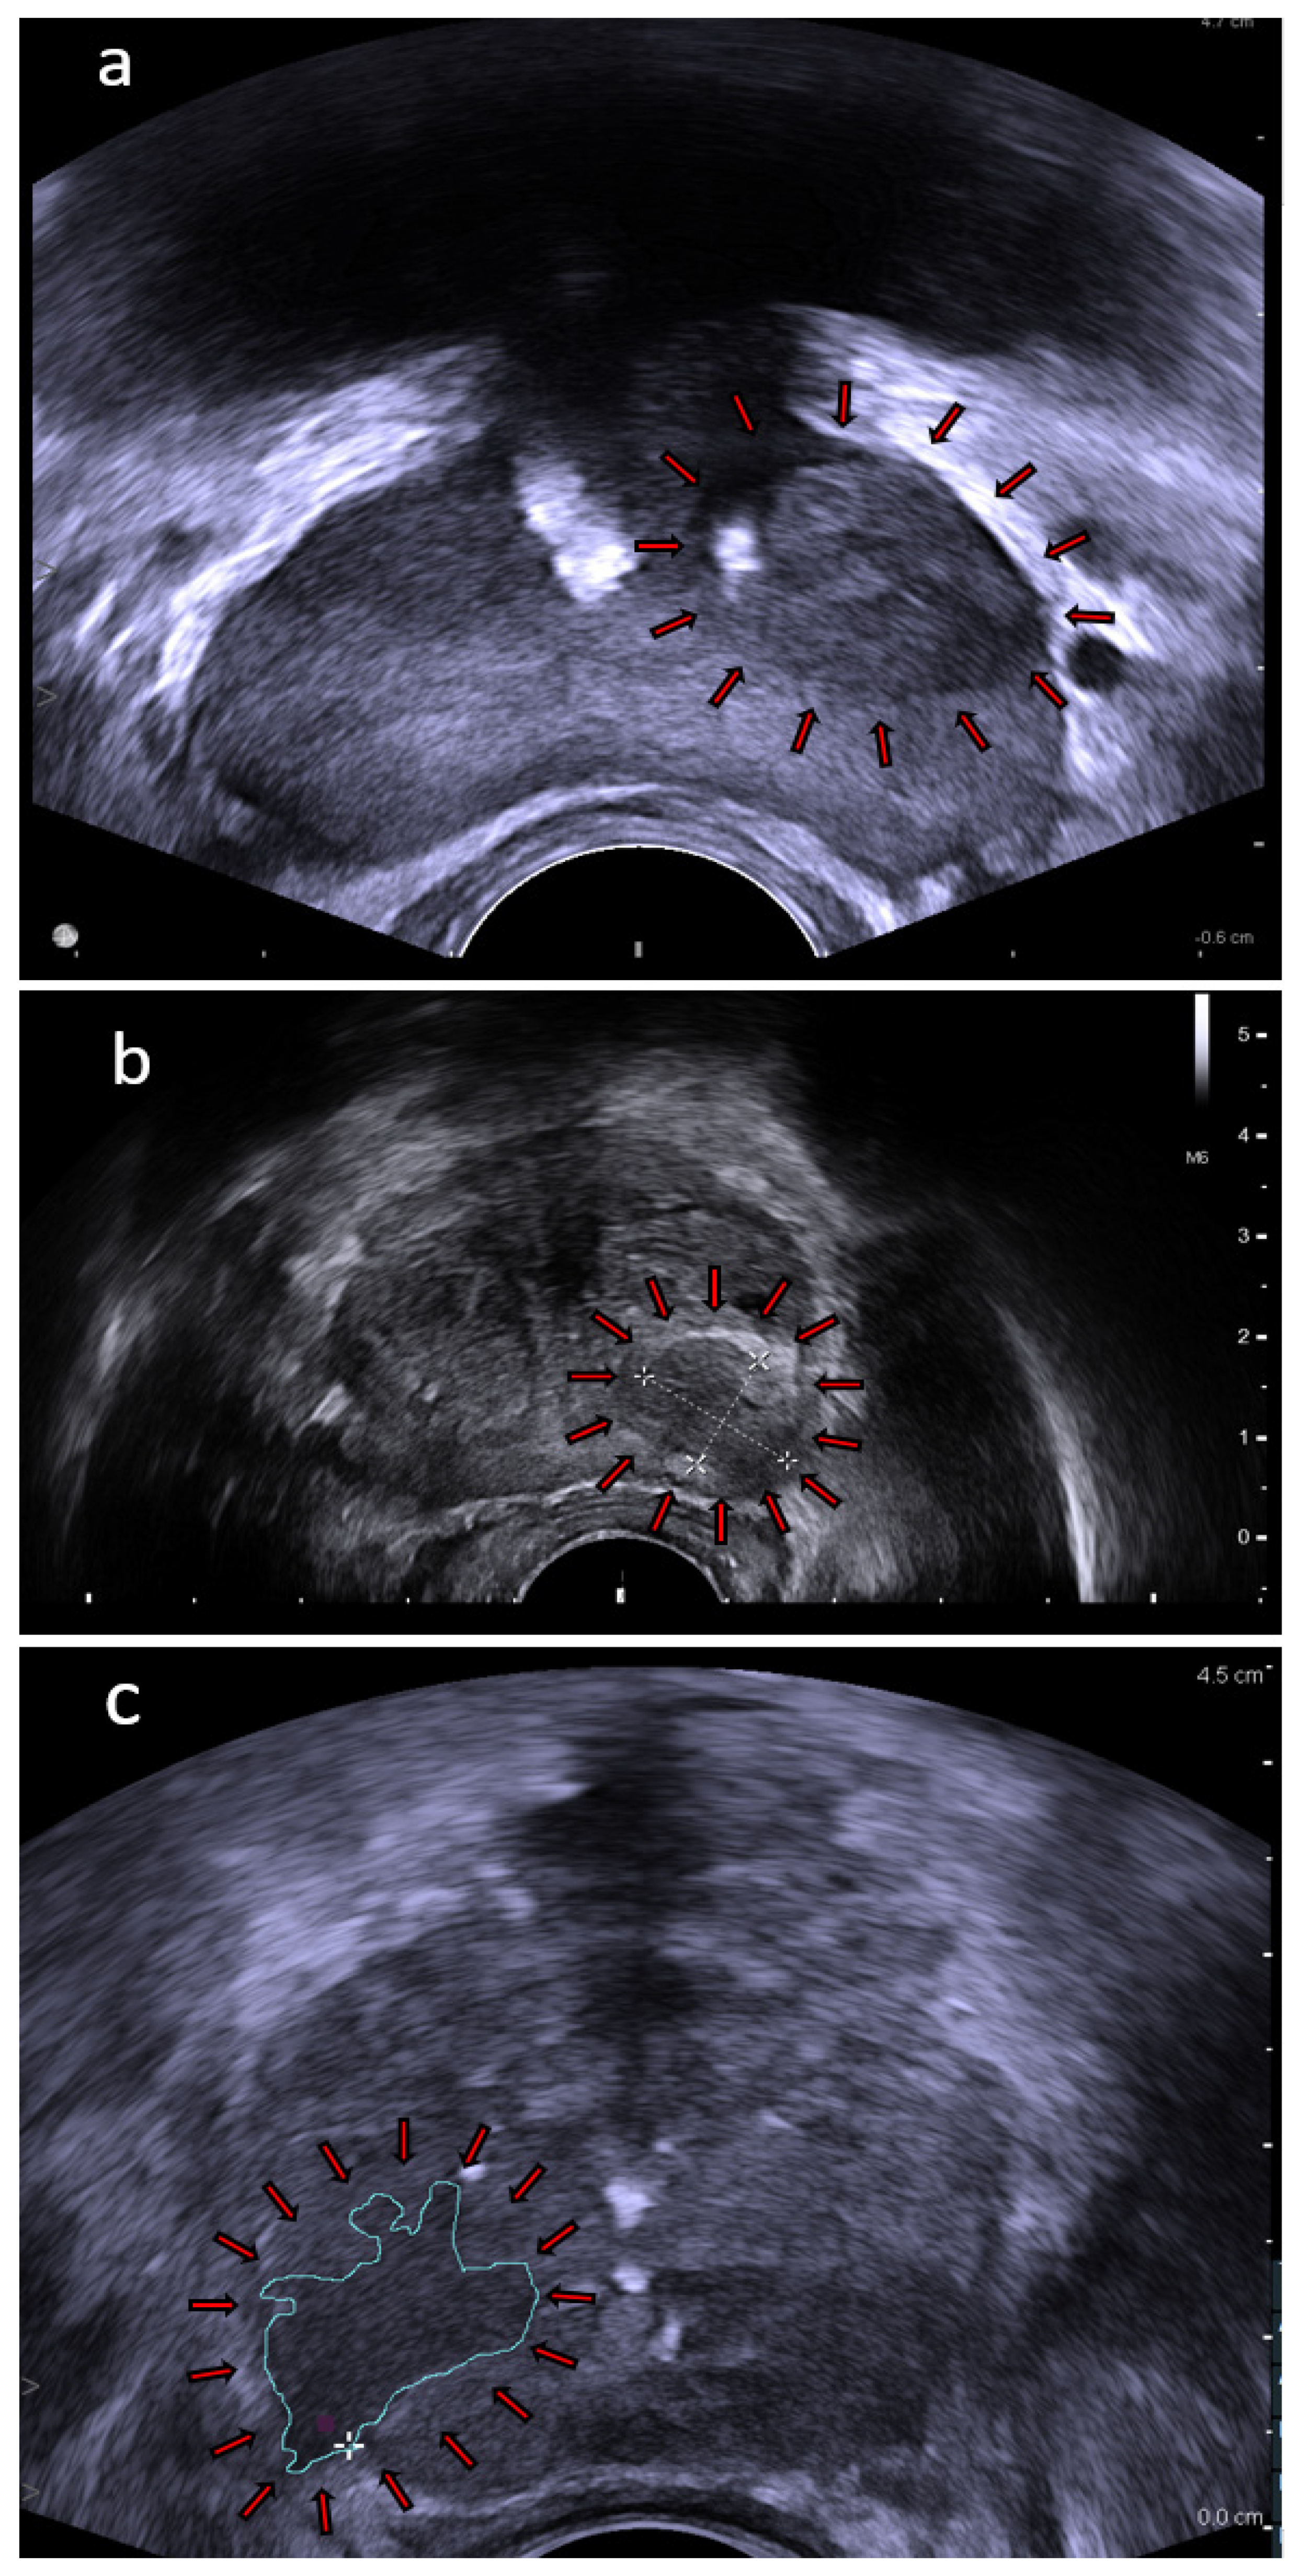

4.1. High Frequency Micro-Ultrasound

4.2. Contrast-Enhanced Ultrasound

4.3. Shear-Wave Elastography

4.4. Multiparametric Ultrasound